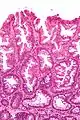

La partie profonde des glandes est souvent élargie, a tendance à se diviser en deux ou trois branches et à s’horizontaliser, c'est-à-dire à se disposer parallèlement à la musculaire muqueuse et non pas perpendiculairement à elle, comme dans les polypes hyperplasiques conventionnels et les adénomes festonnés traditionnels.